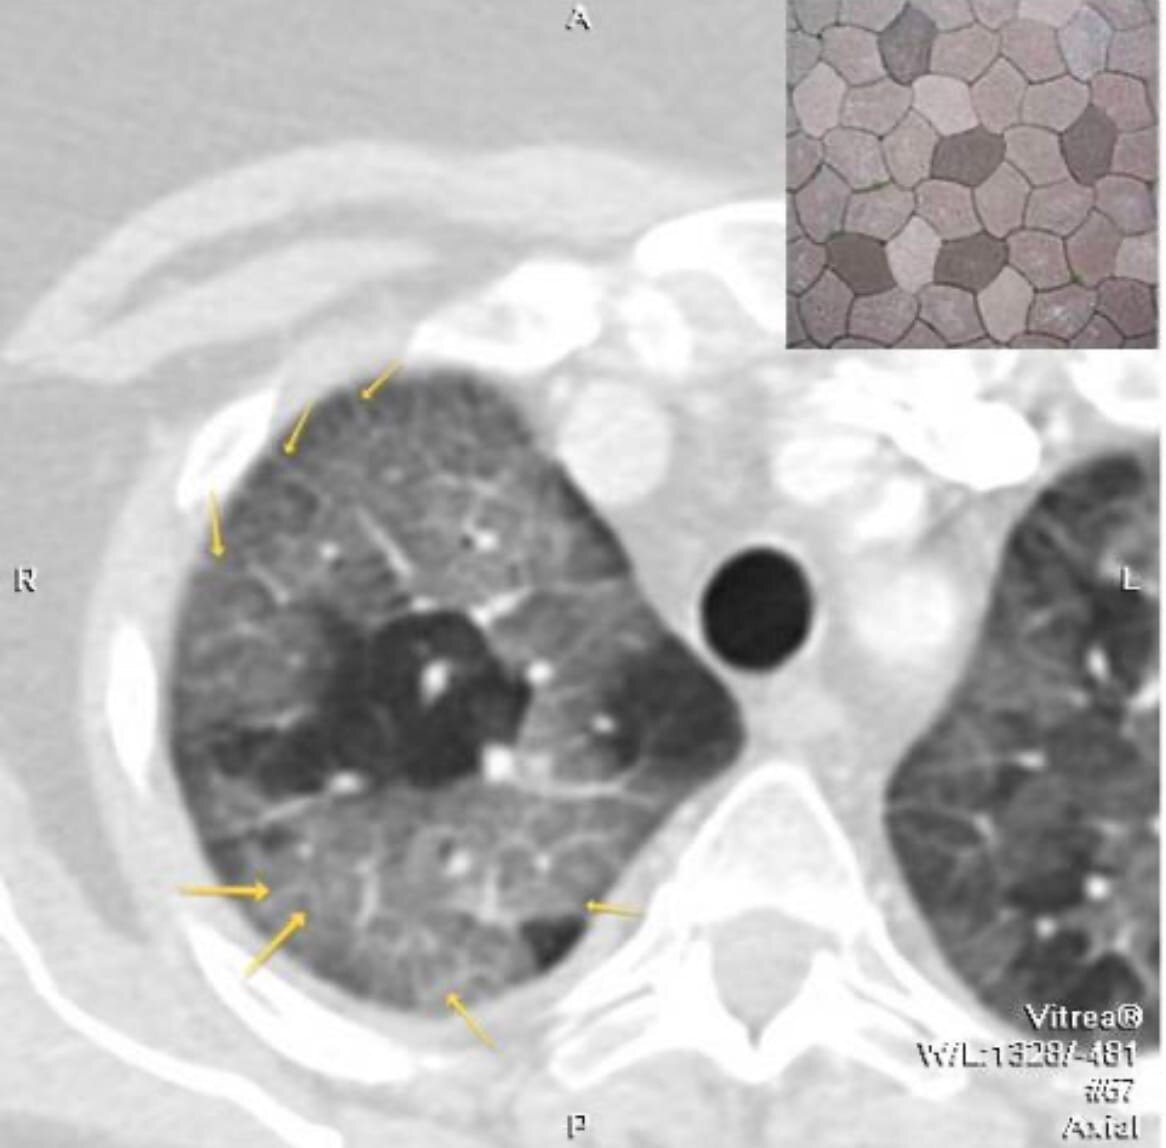

Действительно, многие из вас могли прочитать в своих заключениях КТ о симптоме булыжной мостовой (на иллюстрации) или симптоме консолидации. А уж о симптоме матового стекла слышал буквально каждый первый, я уверен! Все эти номенклатурные неофициальные единицы хорошо известны специалистам лучевой диагностики и широко применяютс

Действительно, многие из вас могли прочитать в своих заключениях КТ о симптоме булыжной мостовой (на иллюстрации) или симптоме консолидации. А уж о симптоме матового стекла слышал буквально каждый первый, я уверен!

Все эти номенклатурные неофициальные единицы хорошо известны специалистам лучевой диагностики и широко применяются не только в России, но и во всём мире. Подобная унификация позволяет добиться лучшей коммуникации между специалистами из разных стран, структурирует знания, упрощает рентгенологические протоколы, делая их более изящными. Ведь, как говорит один мой знакомый мудрый доктор, рентген - это искусство!..